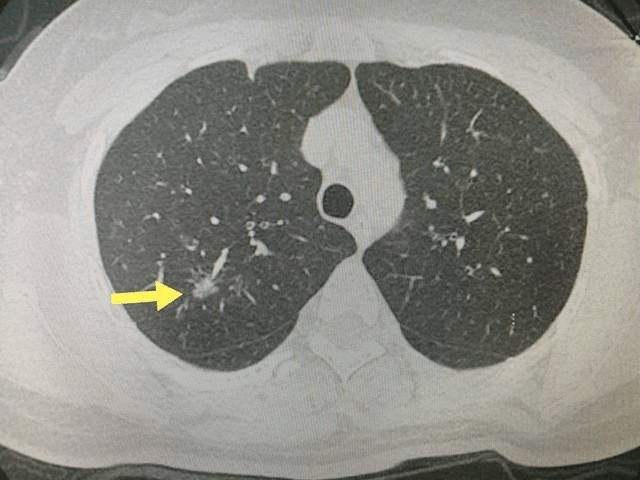

37岁的刘女士 , 两年前 , 在单位组织的体检中 , 被查出左下肺和右上肺各有一个磨玻璃结节 , 体检报告建议胡女士完善CT检查 , 随访 。 磨玻璃结节意味着什么 , 刘女士没有任何概念 , 也没有在意 。

直到去年年初的一次复查 , 肺部CT报告提示左下肺混合磨玻璃结节已经到了需要手术的地步 。 于是 , 在朋友的介绍下 , 她经过比较 , 最终选择了上海市肺科医院进行手术 。 通过进一步就诊 , 刘女士最终被确诊为早期肺癌 。 术后 , 刘女士在主治医生的建议下进行了4个疗程的化疗 , 然后又接受了中医调理 。

【肺癌 患肺癌的女高管告诫女性朋友们:别在自己脸上折腾太多,或增加健康风险】然而 , 祸不单行 。 年前的一次复查结果显示她右肺上叶的小结节已从原来的5mm增大到了8mm , 不想再经历手术之苦的她选择了做射频消融 。